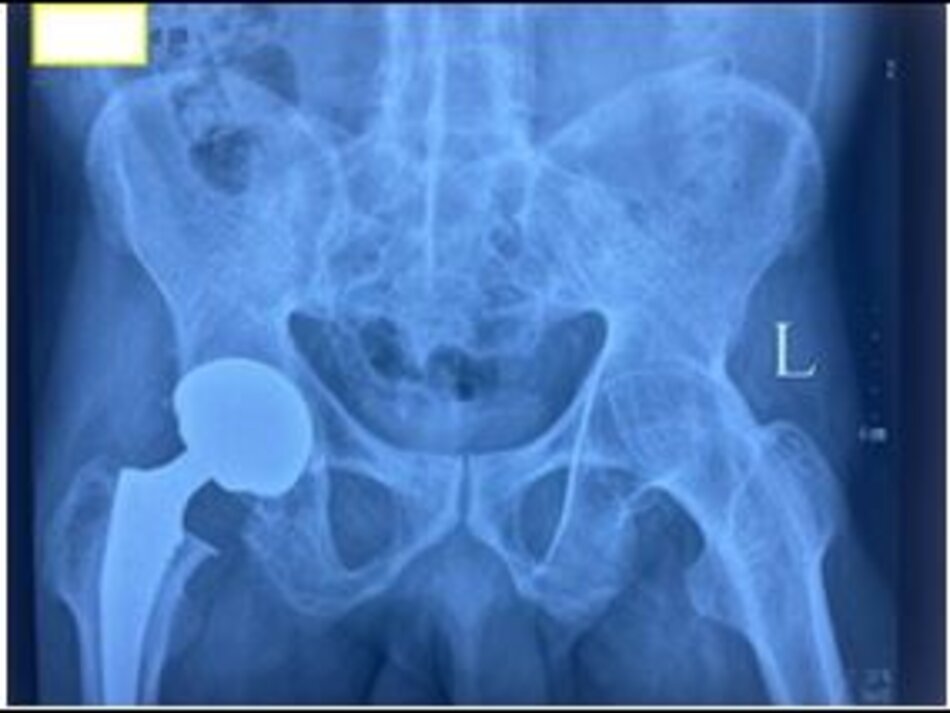

Xquang sau mổ. Hình ảnh khớp háng trái nhân tạo

Xquang trước mổ. Hình ảnh dính hoàn toàn khớp háng trái. BN nam 45 tuổi, viêm dính khớp háng 2 bên gây ra tình trạng khớp háng cứng chắc, không thể gấp duỗi

Xquang sau mổ. Hình ảnh khớp háng trái nhân tạo. Xquang sau mổ, BN đã có thể cử động khớp háng và tập đi lại ngày thứ 3 sau phẫu thuật